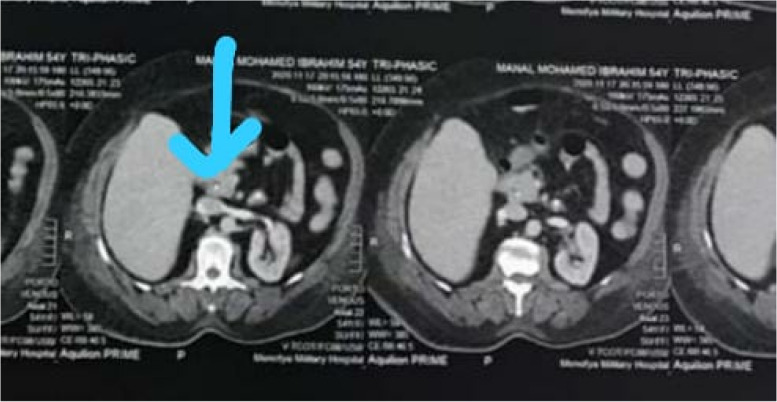

Also, immediate point of care ultrasound (POCUS) revealed a right hepatic lobe focal lesion measuring (10×10cm), along with an evident stent inside the common bile duct (CBD) (Fig. 1). A consecutive computerized tomography scan of the abdomen confirmed the right lobe focal lesion as a complex abscess occupying large area (Figs. 2 and 3).

The CBD was cannulated after strenuous extraction of a long (20 cm) catheter that was largely displaced into the duodenal lumen. Cholangiogram revealed mildly dilated CBD with multiple large stones accompanied by mildly dilated central biliary radicals. Surprisingly, an old stent was hardly seen inside the dilated CBD, with mild dilatation of the intrahepatic biliary channels (Figs. 4, 5, and 6).